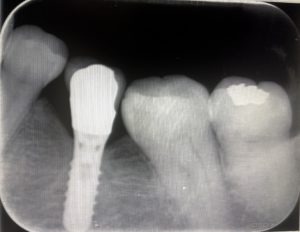

予後32年のインプラント

久しぶりに32年前にオペをした患者さんがいらっしゃいました。自分の一番古い症例です。その当時、インプラント治療は大丈夫なのかと言われていた時代です。今ではどこの歯科医院でもインプラント治療をしているのが嘘のようです。